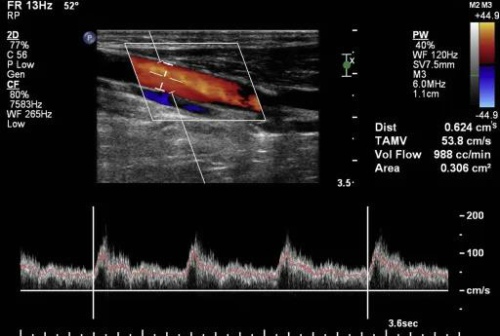

超声是一种成像方式,除了具有良好的耐受性和广泛使用性外,还被认为是评估阴茎勃起功能障碍极好方法,常用是阴茎彩色多普勒超声检查(CDDU)。

阴茎海绵体是均质的圆柱形结构,具有中等回声和均匀的回声纹理。

海绵体内衬白膜,白膜是一种薄膜,阴茎松弛时厚度约为 2 毫米,勃起时厚度约为 0.25 毫米,白膜表现为围绕语料库的薄的线性高回声结构(通常厚度小于2毫米),在海绵体之间,经常可以看到后部声影区域,它对应于阴茎间隔。

在两个海绵体中,海绵体动脉被视为狭窄的管状结构,纵平面有回声壁,横平面有回声点。

背静脉出现在阴茎背侧,表现为无回声的可压缩小管,通常在彩色多普勒超声上可检测到血流。